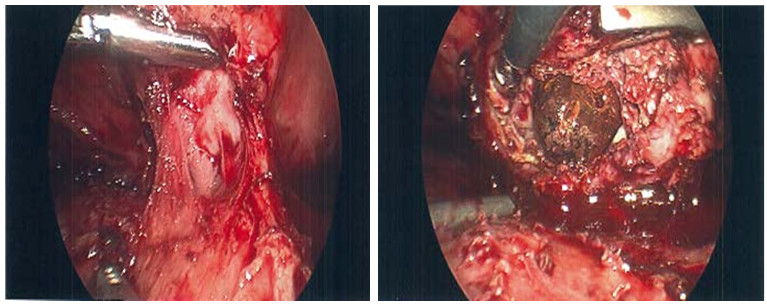

On physical exam, he was a febrile with normal vital signs and had a tender epigastrium without peritonitis. Given his cardiac comorbidities and chest pain, a coronary event was first ruled out with troponins and EKG. Other laboratory studies were significant for a WBC of 19.2. On imaging work up, his CXR showed no pneumoperitoneum and no acute cardiopulmonary processes. Given his history of upper abdominal pain and a h/o difficult laparoscopic cholecystectomy, a right upper quadrant ultrasound was obtained which showed a hypo echoic collection superior to the liver with a hyperechoic focus in it (Figure 1). A CT scan was obtained which showed a subphrenic fluid collection with a 2cm stone in it, a subhepatic fluid collection and moderate pericardial effusion. There was also a concern for a pericardial-peritoneal fistula (Figure 2).

Figure 1 A right upper quadrant ultrasound was obtained which showed a hypo echoic collection superior to the liver with a hyperechoic focus in it.